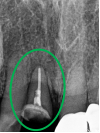

治療内容

歯髄(神経および血管)まで到達する大きな虫歯でしたので、抜髄(歯髄を取り除く)をし、ファイバーコアをいれ、オールセラミック冠を被せました。